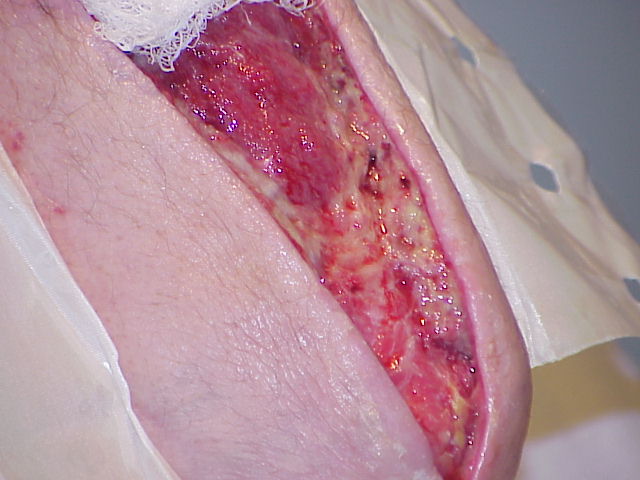

Matt's Arm Surgery due to a bacterial infection.

(Necrotizing Fasciitis)

June and July 2000

The following pictures were taken by my

brother Charles.